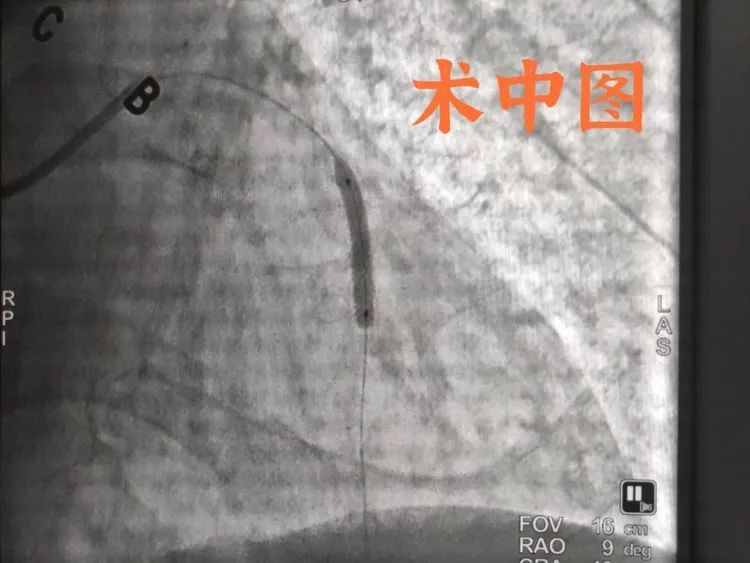

经过充分的评估与沟通,东方心内团队汪蛟龙主任等为其行DSA引导下冠状动脉造影术+药物球囊,将闭塞的前降支血管行药物球囊。术后,徐师傅症状立即缓解,很快康复出院,对东方心内的技术赞不绝口。“东方医院看病很有技术,十年前就是在东方医院放的支架。这次我还是选择东方医院,就是因为他们看得好。看病好,服务好,花钱少。国家政策好,他们医院也好,我们老百姓有福气啊!”

广济医院心内科桂陈主任介绍,药物球囊是冠心病介入治疗近几年出现的一种技术,全称药物涂层球囊,通过局部向动脉血管壁释放内膜增生的药物,从而起到抑制内膜增生,达到抑制血管再狭窄的目的。它的特点是“介入无植入”。对于冠心病介入治疗支架植入术后出现的支架内再狭窄,以及小血管(如2.5mm以下的血管)病变、分叉病变等疾病患者提供了新的治疗途径,尤其是年轻患者的治疗更具有优势。